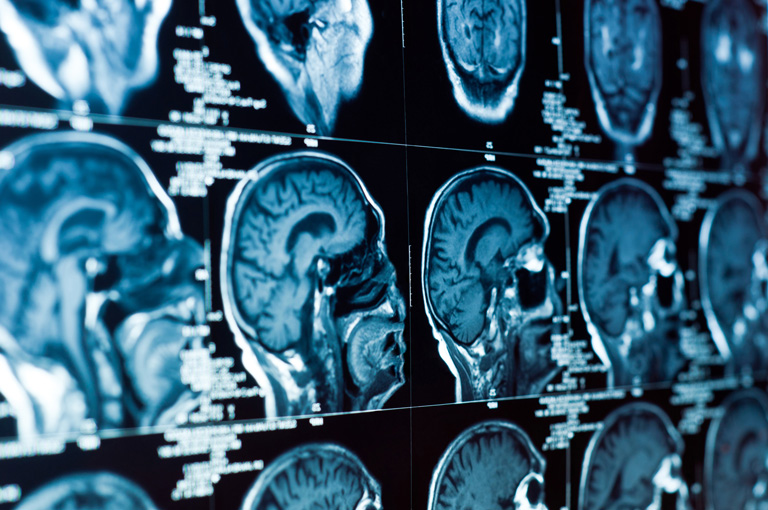

Hipertenzija oštećuje krvne žile, neurone i bijelu tvar u mozgu mnogo prije nego što stanje uzrokuje mjerljiv porast krvnog tlaka, tvrdi nova studija. Promjene pomažu objasniti zašto je hipertenzija glavni faktor rizika za razvoj kognitivnih poremećaja, poput vaskularnog kognitivnog oštećenja i Alzheimerove bolesti.

Jednako tako, studija je pokazala, da hipertenzija može izazvati rane promjene u ekspresiji gena u pojedinačnim moždanim stanicama koje bi mogle ometati razmišljanje i pamćenje.

Interneuroni, moždane stanice koje reguliraju živčane signale između motornih i senzornih neurona, također su bili oštećeni. To je dovelo do neravnoteže između inhibitornih i ekscitacijskih signala poput one koja se vidi kod Alzheimerove bolesti. Osim toga, oligodendrociti koji obavijaju živčana vlakna mijelinom nisu pravilno eksprimirali gene odgovorne za njihovo održavanje i zamjenu. Bez dovoljno oligodendrocita za održavanje zdravih mijelinskih ovojnica, neuroni na kraju gube sposobnost međusobne komunikacije, što je ključno za kognitivnu funkciju.